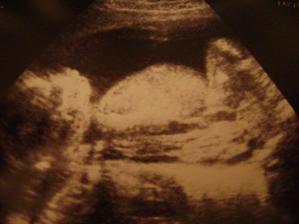

Náš malý drobček 🙂